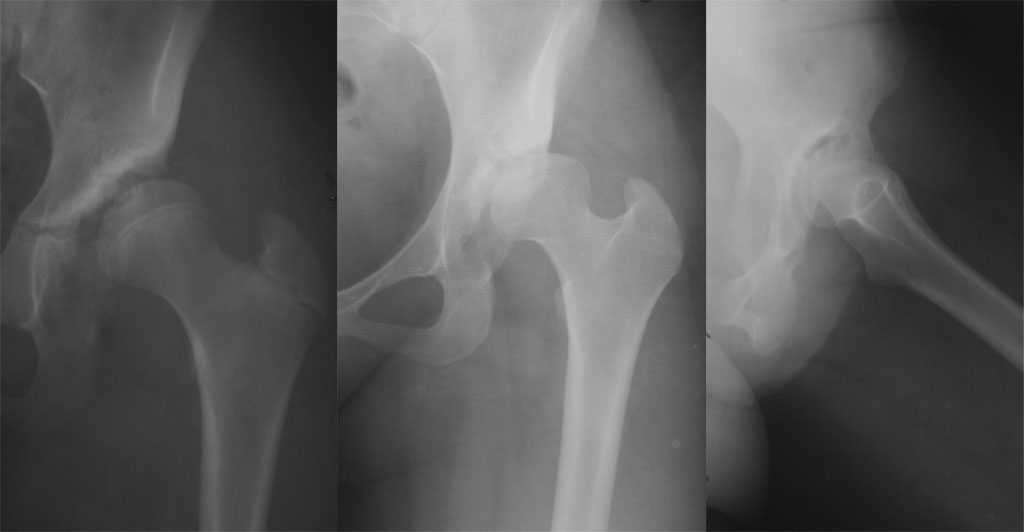

Как раз к обсуждению. Обратилась за косультацией 21-летняя девушка с жалобами на боли в левом тазобедренном суставе.

По-моему рентгенологическая картина вполне укладывается в пнятие "диспластический коксартроз". Поясните, на чем основан Ваш диагноз?

Если исходить из наличия диспластического коксартроза, то, поскольку дегенеративные изменения выражены достаточно сильно (особенно отчетливо на боковой проекции), стоит рассмотреть тотальное эндопротезиование. Естесственно, эндопротез должен быть адекватным возрасту.

Почему нет обзорной рентгенограммы таза? Обратите внимание на лилню Шентона, на дефект покрытия коловки, я думаю что вся проблема в крыше вертлужной впадине, и нужно просто её создать, можно подумать о остеотомии таза + костную пластику на усмотрение.

Господа, видимо название темы ввело вас в заблуждение. Спасибо уважаемому администратору(a proros, с днем рождения!!!), что выделил отдельной темой мой первый пост, Однако это создало впечатление о затрудненности постановки диагноза. Поверьте, ни у кого не вызывает сомнений, что мы имеем дело с диспластическим коксартрозом, подвывихом головки бедренной кости. Просто момент обращения за консультацией совпал по времении с активным обсуждением схожего случая. в эту же тему я и поместил свой "ответ". Как и большинство моих коллег "взрослых" ортопедов я, к сожалению, практически никакого представления не имею об особенностях детской ортопедии. Налицо тот разрыв, на который указывал Плющев в своем труде "Диспластический коксатроз". Я считаю, что девушка слишком молода для эндопротезрования тазобедренного сустава. Что делать? Рекомендовать консервативное лечение (лечение???), готовя ее морально к грядущему эндопротезированию или есть возможности хирургической коррекции взаимоотношения суставных поверхностей, подобных периацетабулярной остеотомии.

Уважаемый коллега! Из двух снимков в прямой проекции первый, вероятно, был сделан в возрасте пациентки от 15 до 18 лет (отсутсвует синостизирование головки о б/вертела), на том этапе целесообразно было выполнить ацетабулопластику типа Хиари. Второй снимок, вероятно, отражает настоящий возраст пациентки, на нем тяжелый деформирующий артроз (и конечно нестабильный сустав)с формированием уже конфликта головки и впадины по типу "bone to bone", что является показанием к эндопротезированию и учитывая молодой возраст пациентки - с использованием ревизионной ножки протеза.